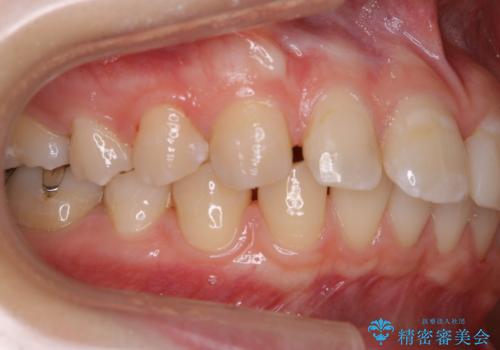

歯並が、がたついている場合はなおさら汚れが溜まりやすいです。矯正治療前や矯正中、定期的にPMTCをすることで、矯正治療中の歯肉トラブルを防ぐことにつながります。